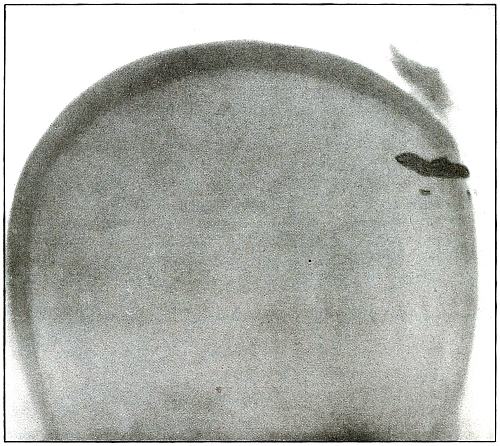

Plate 1.

_

[Pg 13]

Rifle—Plate 1.

HEAD.

Gunshot Fracture of the Skull, with Lodgment of the Missile.

The bullet in this case was so badly deformed by ricochet that part of both core and jacket were lost. While the appearance of the shadow seems to indicate a direct impact of the nose of the bullet, the line of contact with the skull must have been tangential, with some laceration of the scalp; otherwise a cursory examination of the scalp wound would have revealed the slightly protruding end of the bullet. The dark shadow above the projectile is due to material used in dressing. The great thickening of the scalp in the region of the wound shows a marked cellulitis. Small particles of the lead core of the bullet can be seen about the wound.

In such cases there is often a marked infection of the scalp without extension of infection to the cranial cavity, except from neglect. This is a case, though apparently simple, in which the radiograph was necessary for correct diagnosis without exploration.

The treatment in such cases is conservative, with removal of the projectile and care of the superficial infection or subsequent complications. [Pg 14]